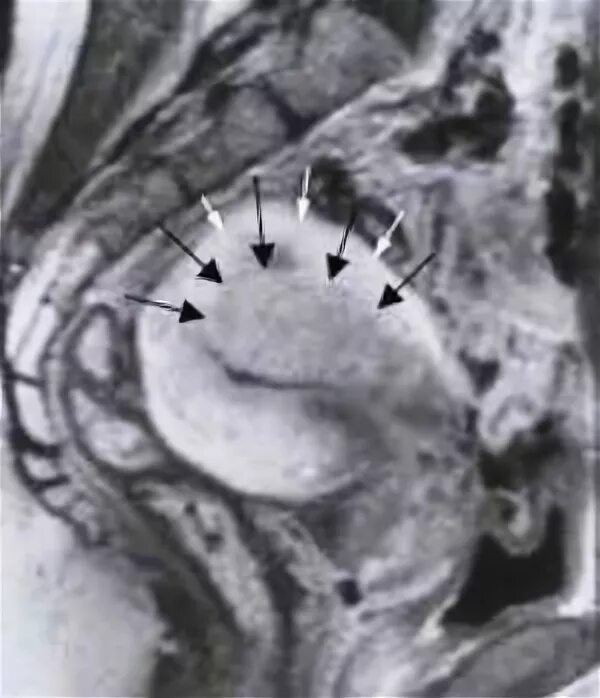

Диффузный аденомиоз матки мрт. субмукозная миома матки мрт.

Очаговый аденомиоз мрт. локальный аденомиоз мрт.

Ретроцервикальный эндометриоз мрт. очаговый аденомиоз матки мрт. эндометриоз аденомиоз матки. ретроцервикальный эндометриоз на узи.